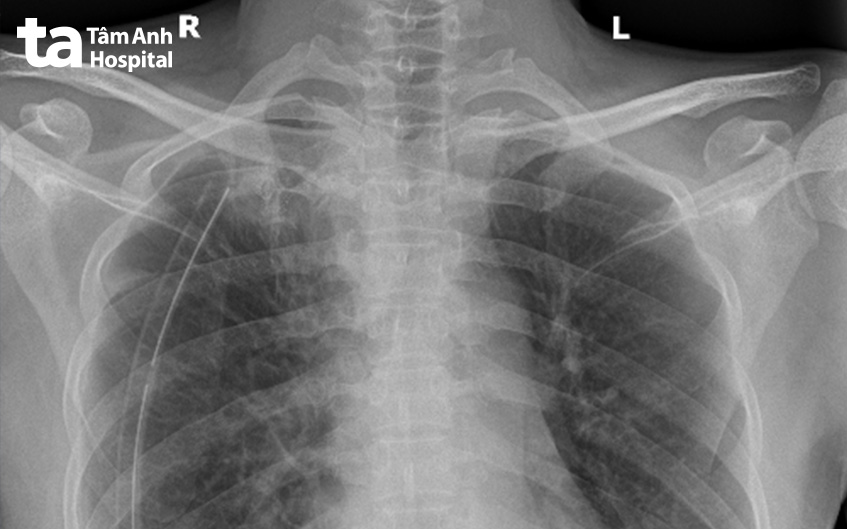

Sau mổ, bệnh nhân hồi phục nhanh, đau vết mổ ít, chụp X-quang kiểm tra thấy phổi nở tốt, dẫn lưu hết rò khí và được rút sau mổ 36 giờ. Bệnh nhân xuất viện sau 3 ngày với tình trạng hô hấp bình thường.